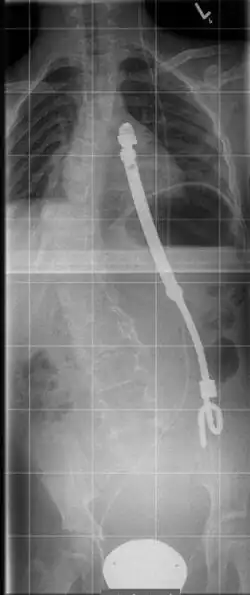

Das Instrumentarium wird eingesetzt, um bei einer schweren Thoraxdeformität einen zu kleinen oder zu schmalen Rippenthorax aufzuweiten und aufzurichten. Es besteht aus einer ausziehbaren „Titanrippe“ in gebogener Form mit mehreren Löchern in Reihe zur Fixierung in der gewünschten Länge. Nach jeweils 6 Monaten kann eine Verlängerung operativ erfolgen. Die Fixierung erfolgt zwischen zwei Rippen oder zwischen einer Rippe und dem Beckenkamm. Dadurch erfolgt eine indirekte Aufrichtung der deformierten Wirbelsäule und damit ergibt sich eine Volumenzunahme des Rippenthorax mitsamt der Lunge.